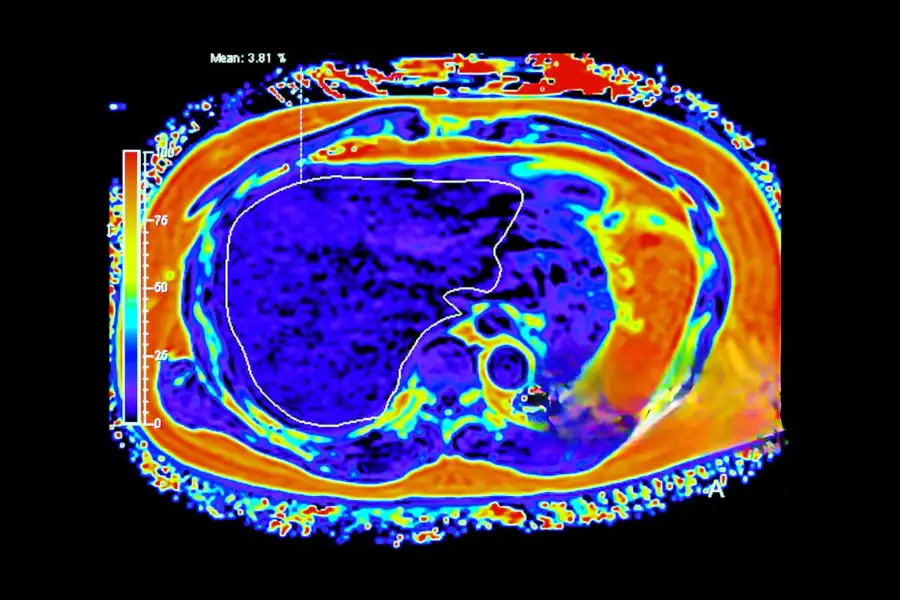

МРТ печінки з контрастом: діагностика метастазів та пухлин

На ранніх етапах захворювання може не проявлятися жодними симптомами — біль, втома або жовтяниця з’являються вже при значному ураженні тканин. Саме тому МРТ печінки з контрастом відіграє вирішальну роль у ранній діагностиці раку. Завдяки високій чутливості методу можна виявити навіть невеликі новоутворення чи метастази, які ще не видно на УЗД або КТ.

МРТ печінки з контрастом дає змогу з високою точністю розрізняти різні види пухлин — як злоякісні, так і доброякісні. Як зазначає онколог Євгеній Гірагосов: “Завдяки введенню контрастної речовини лікар бачить не лише форму та розміри утворення, а й особливості його кровопостачання, структури й динаміки накопичення препарату. Це дозволяє диференціювати тип пухлини печінки без необхідності інвазивних процедур”.

Таким чином, МРТ печінки з контрастом дозволяє побачити широкий спектр пухлин — від небезпечних форм раку до доброякісних утворень, які не несуть загрози життю. Завдяки характерним ознакам накопичення контрасту лікар може визначити природу новоутворення, стадію захворювання та вибрати оптимальну тактику лікування без потреби в біопсії.